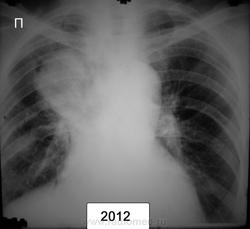

Ж.1938г.р. жалоб нет, более ранние рентг.описания - туберкулома

По-моему это типичный периферический рак

С уже "централизацией". Вопрос-больной наблюдается не мало-других мыслей кроме туберкуломы не было и он нигде больше не обследовался? Или это неизвестно?

был периферический кадато, стал централизоваться , пророс по бронхам как по рельсам :-)

месные фтизиатры были за туберкулому

обласные за туберкулому

КТ не проводилось

должны были наблюдать в динамике , но характер тени уж совсем не за туберкулому!